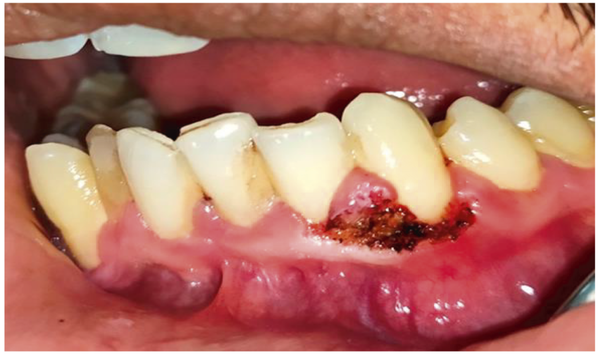

Comparative Evaluation of Efficacy and Safety of the Diode Laser (980 nm) and Sclerotherapy for the Treatment of Oral Pyogenic Granuloma

Background. Pyogenic granuloma (PG) is a tumor-like, non-neoplastic lesion of the soft tissue that commonly appears in the oral cavity. Various treatment modalities have been discussed, including surgical excision, cryosurgery, curettage, electrodessication, corticosteroid injection, sclerotherapy, and lasers. This observational retrospective study compared effectiveness between diode lasers and sclerotherapy for PG treatment. Materials and Methods. From July 2016 to January 2021, data of oral P